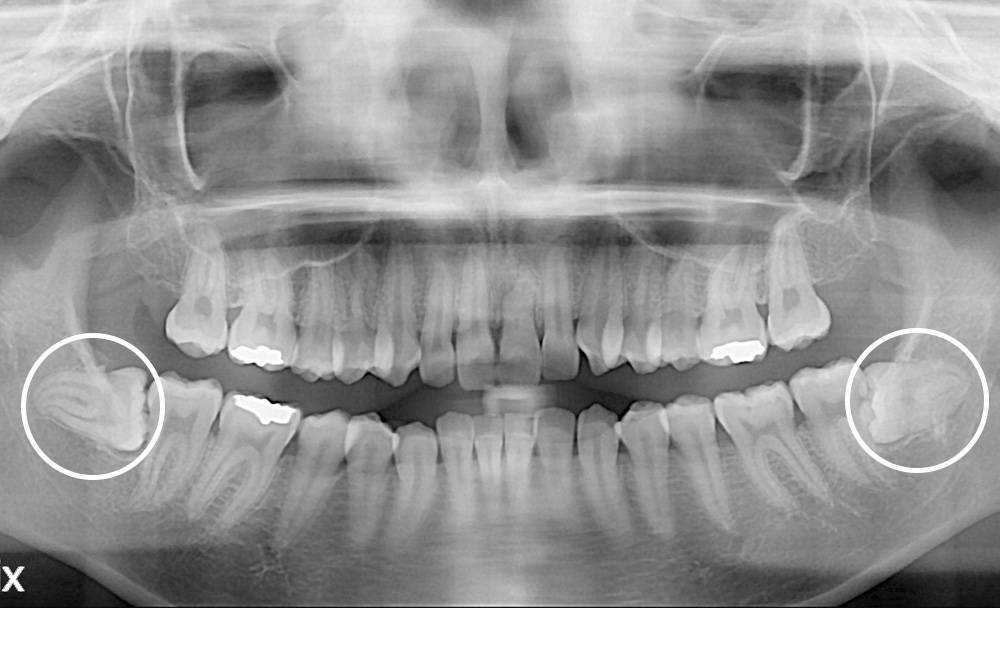

[사랑니] 매복 사랑니 발치

치료전 : 2019-08-02

치료후 : 2019-08-19

세종치과는 구강악안면외과학 박사이신 원장님이 발치하는 치과 입니다.